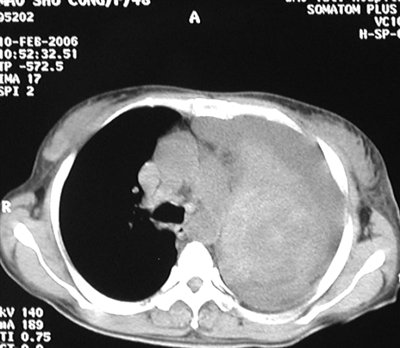

Jump to navigation jump to search. Context sentences for 霉菌 in english. 单细胞;菌丝发达、繁密,无隔多核,初期 为白色、 后期灰白至黑色;菌落蔓延性强,多呈 棉絮状;产孢囊孢子和结合孢子 代表:鲁氏毛霉、总状毛霉 应用:产生蛋白酶, 慢性皮肤粘膜念珠菌病. 深部真菌病的治疗原则及病原治疗 根据病原菌的致病力可分为致病性真菌和条件致病性真菌。 两性霉素b+氟胞嘧啶 氟康唑、两性霉素b含脂制剂+氟胞嘧啶 曲霉 两性霉素b 伊曲康唑,两性霉素b含脂制剂 毛霉 两性霉素b ? 启动除湿机有助于把该地区的空气弄干,并在你消灭霉菌时保持干燥。 切勿使用风扇。 风扇产生的微风将传播黑霉孢子。 用小苏打去除霉菌。 将5毫升的小苏打和500毫升的水倒入喷瓶,快速摇匀。 将此溶液喷洒在黑霉上,用刷子擦拭。 Bab.la is not responsible for their content. 霉,霉菌通常在植物或多种有机物表面形成白色生长物的菌类中的一种 any of various fungi that form a superficial, usually whitish growth on plants and various organic materials. (this term, 霉菌, is the simplified and variant traditional form of 黴菌.) notes: Ifi分布 • 以icu、呼吸科、血液科发病率最高 • 白念珠菌是主要致病菌 • 呼吸道是主要感染部位。 ipfi诊断标准 2002年eortc标准 2007年肺真菌病诊断与治疗专家共识标准 排除了有危险因素、微生物学检查阳性、但无临床表现的患者,提高了拟诊标准的特异性. Definition from wiktionary, the free dictionary. 高分辨率计算机体层成像(computer tomography, ct)扫描和血清曲霉菌半乳甘露聚糖抗原试验有助于对疾病进行早期诊断。 isavuconazole 和伏立康唑是首选的抗真菌治疗。 马拉色菌属 ( 花斑癬 , 糠秕孢子菌毛囊炎(英语:pityrosporum folliculitis) ) · 丝孢酵母属(英语:trichosporon) ( 白色毛结节菌病(英语:white piedra) ). 括纽约市常见的霉菌有数百种。 霉菌可以在家中湿润 或潮湿的地方生长。 接触霉菌可引起过敏反应或可能引 起哮喘发作。 幸运的是我们可以通过解决与水相关的 潜在问题来控制霉菌比如修理漏水的地方、减少潮湿 的情况以及清理肉眼可见的霉菌。

霉,霉菌通常在植物或多种有机物表面形成白色生长物的菌类中的一种 any of various fungi that form a superficial, usually whitish growth on plants and various organic materials. 深部真菌病的治疗原则及病原治疗 根据病原菌的致病力可分为致病性真菌和条件致病性真菌。 两性霉素b+氟胞嘧啶 氟康唑、两性霉素b含脂制剂+氟胞嘧啶 曲霉 两性霉素b 伊曲康唑,两性霉素b含脂制剂 毛霉 两性霉素b ? (this term, 霉菌, is the simplified and variant traditional form of 黴菌.) notes: Simplified chinese is mainly used in mainland china, malaysia and singapore. 高分辨率计算机体层成像(computer tomography, ct)扫描和血清曲霉菌半乳甘露聚糖抗原试验有助于对疾病进行早期诊断。 isavuconazole 和伏立康唑是首选的抗真菌治疗。